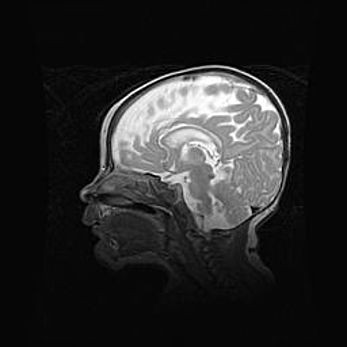

Церебральная ишемия II.

Возраст: 5 дней

Вес: 3400 г

Пол: женский

Окружность головы: 35 см

Срок гестации: 39 недель

Церебральная ишемия – это заболевание, характеризующееся недостаточностью (гипоксией) либо полным прекращением (аноксией) снабжения мозга кислородом по причине закупорки одного или нескольких сосудов. Это приводит к  что метаболическим расстройствам различной степени тяжести в тканях головного мозга, развитию коагуляционных некрозов и гибели нейронов.